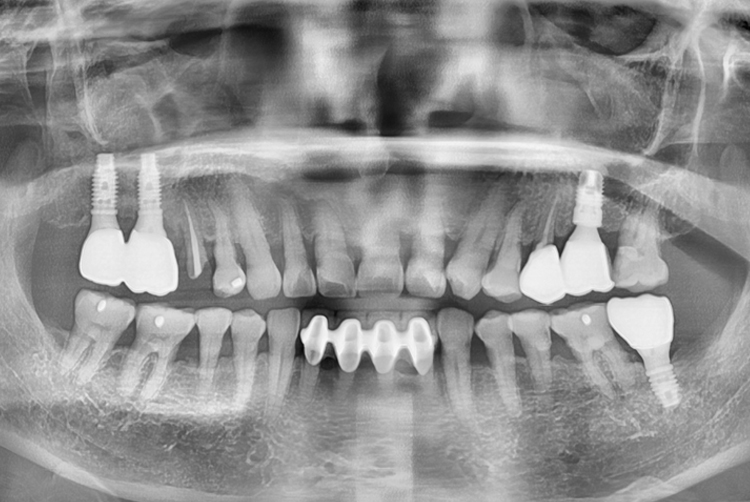

18.02.28.jpg

치료후 : 2018-02-28

세종치과는 많은 환자와 다양한 케이스를 바탕으로 항상 편안한 임플란트 수술을 제공하고자 노력하고,

오래동안 튼튼히 쓸 수 있는 임플란트 수술을 가장 큰 목표로 삼고 있습니다